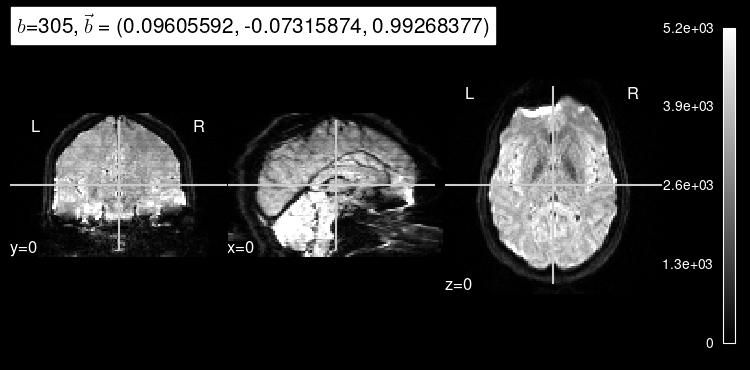

plot_dwi(np.squeeze(data_test[0]), dmri_dataset.affine, gradient=predict_b);

As expected, the b=0 doesn’t look very much like the particular left-out direction, but it is a start!